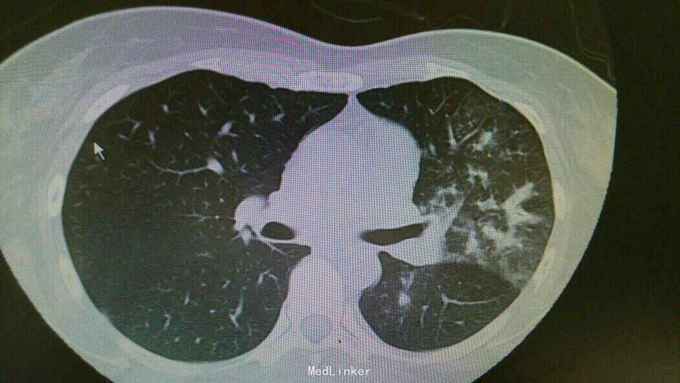

诊断:肺炎支原体费炎。 治疗:入院予以抗感染,止咳化痰等治疗。治疗后复查胸片,左中下肺炎症好转。

随访:嘱患者1周后门诊复查。 讨论:支原体肺炎为常看不典型肺炎,治疗上主要抗感染治疗,一般疗程为3周。临床上主要与肺结核相鉴别。